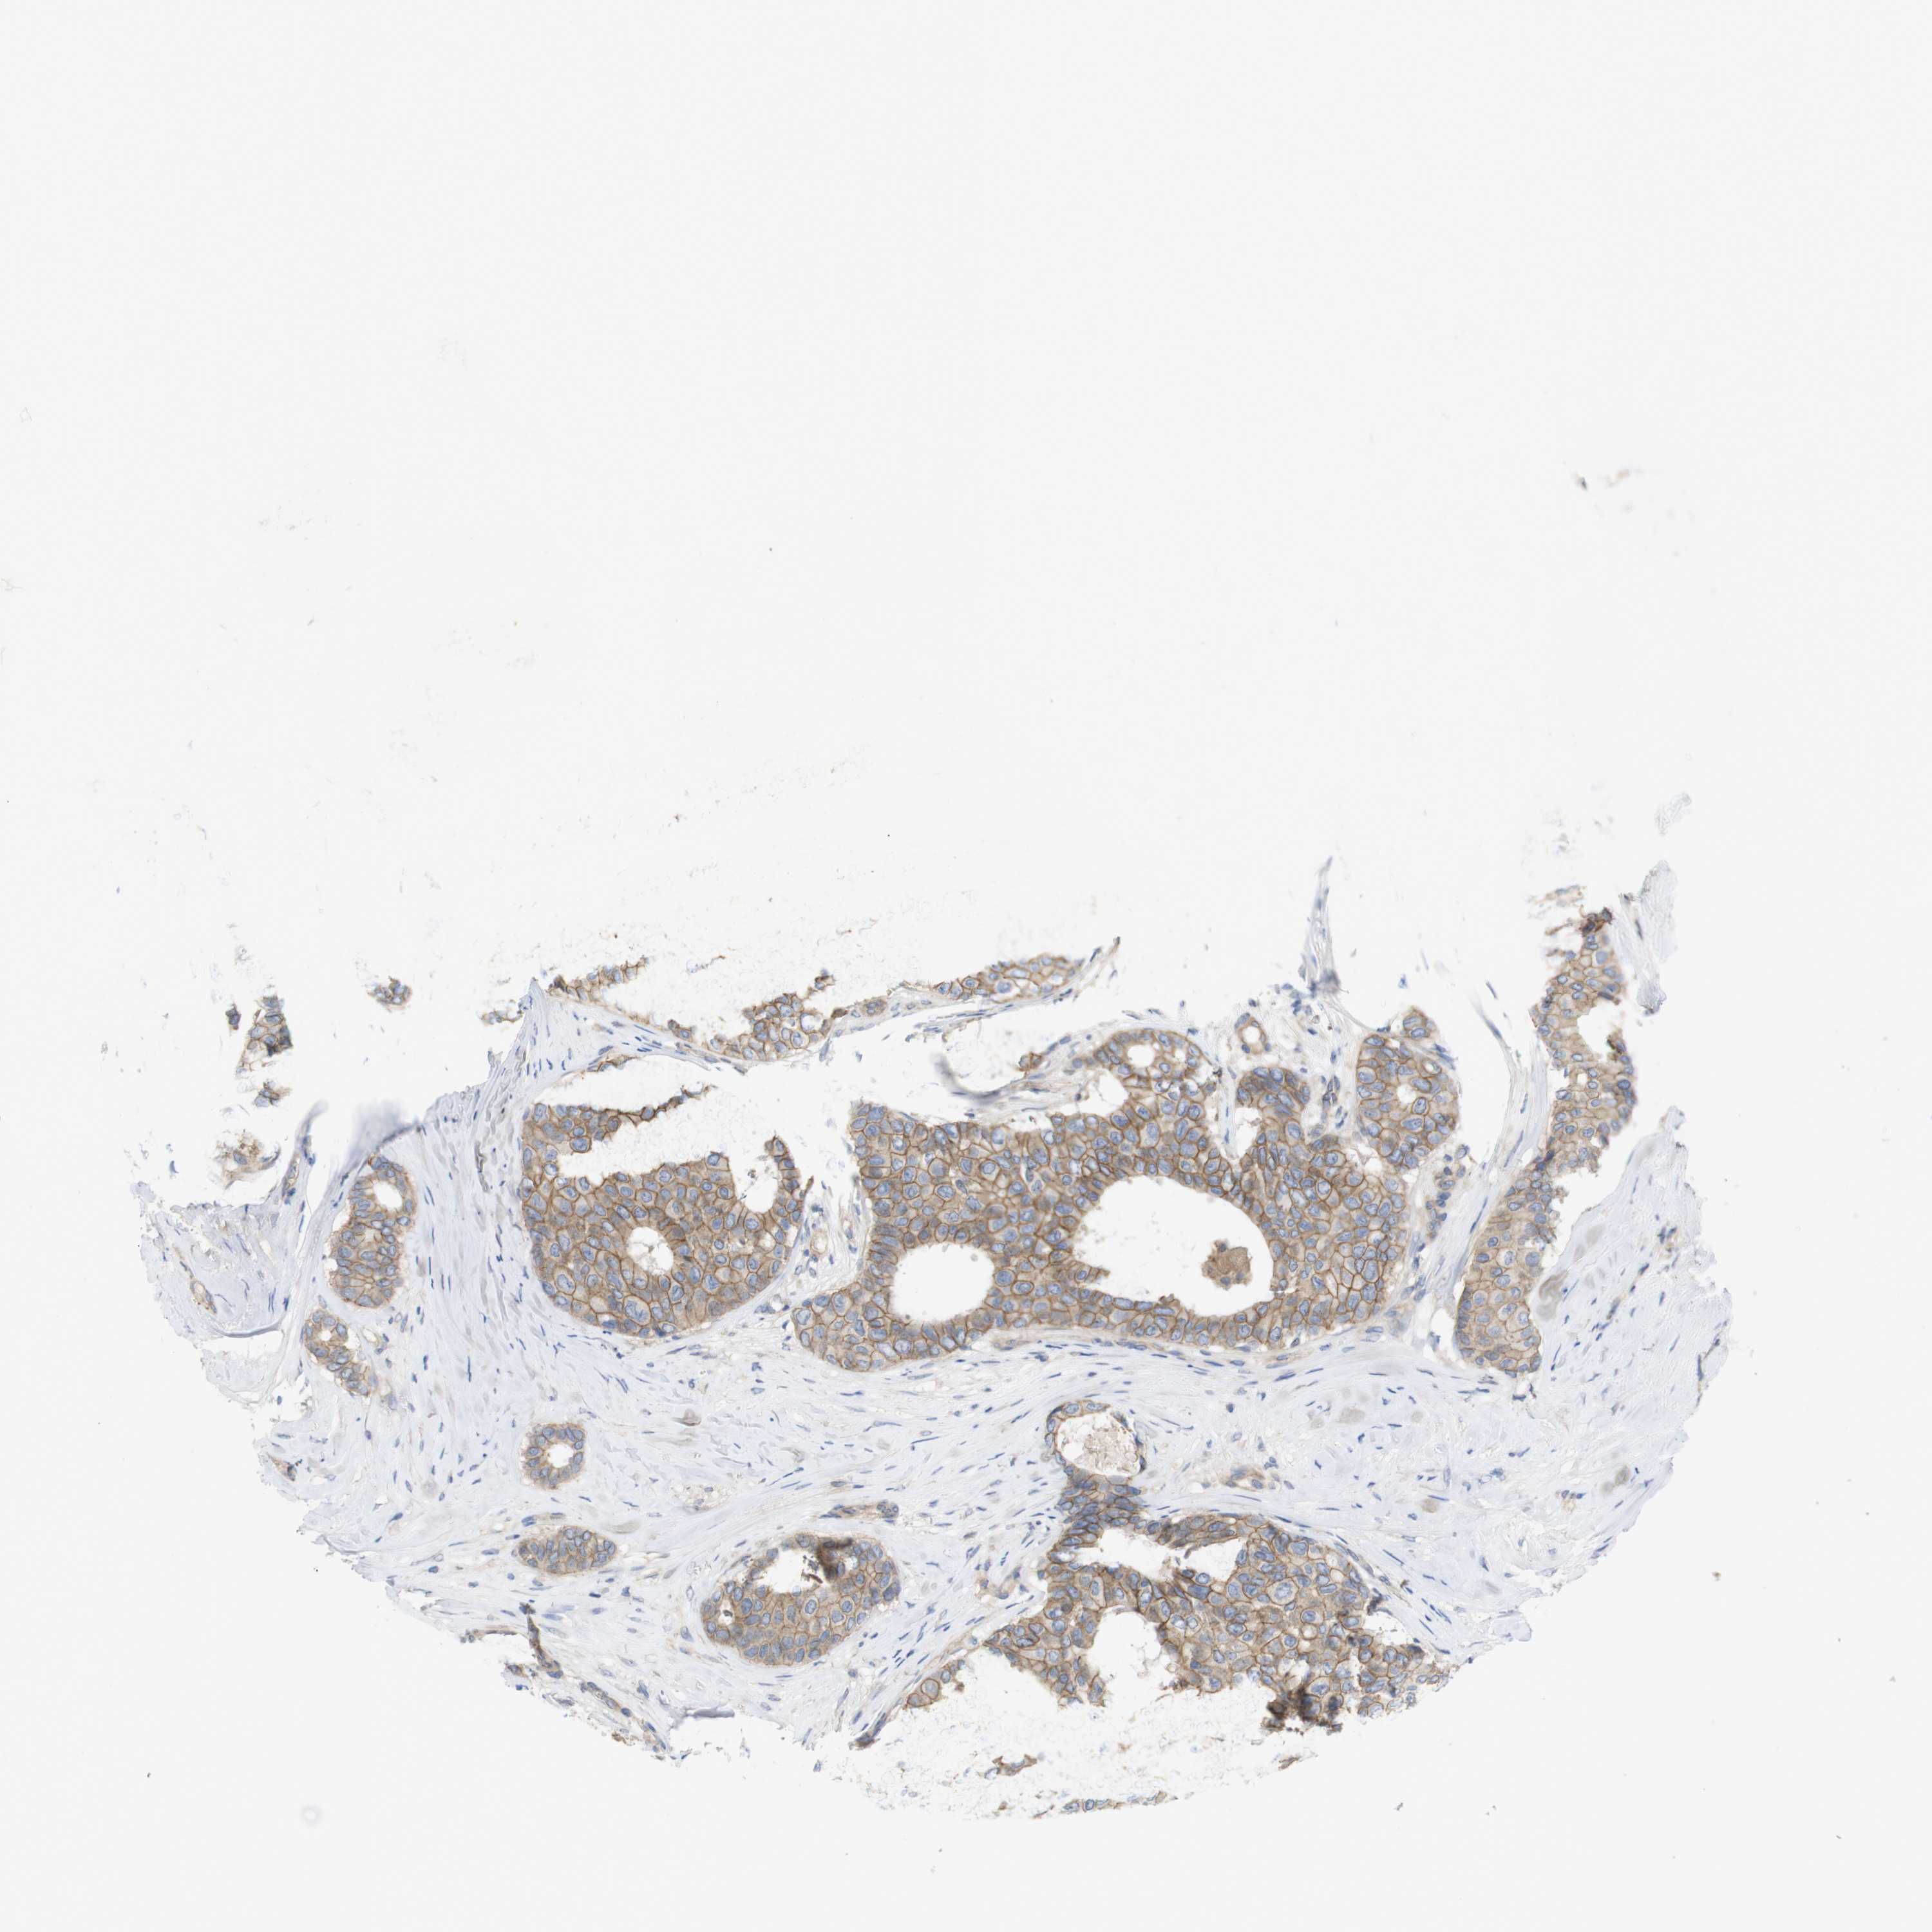

CANCER BREAST CANCER Show tissue menu

BRCA TCGA BRCA VALIDATION PROTEIN EXPRESSION